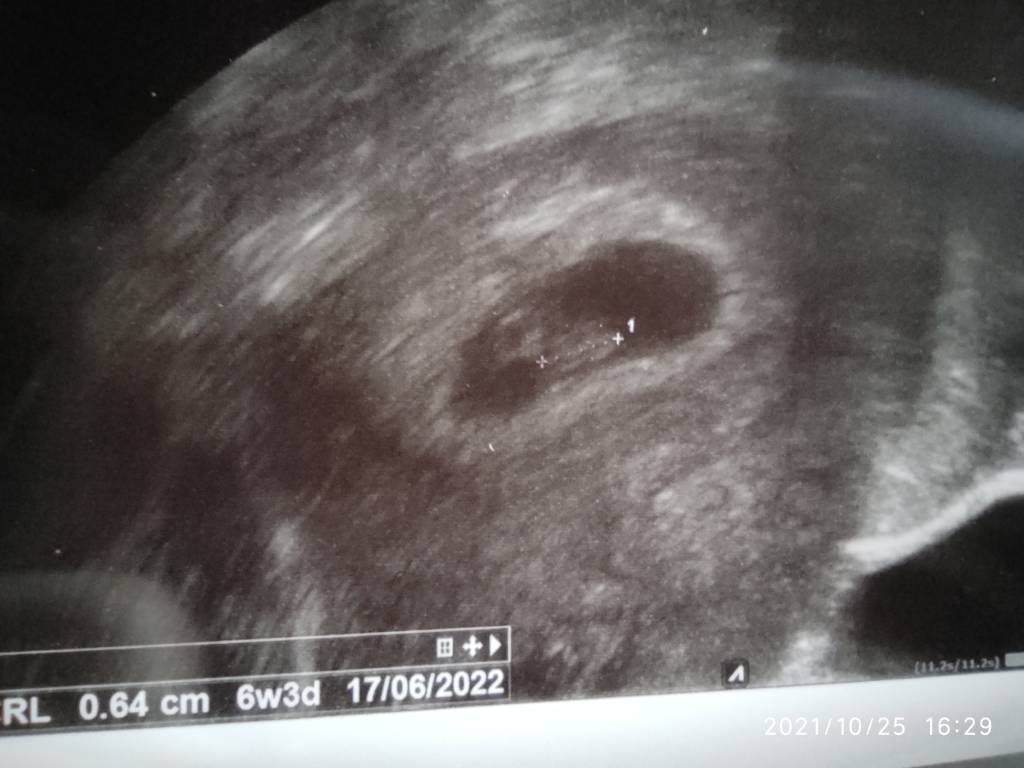

Ja już też po wizycie... Tak jak myślałam - będę świrować, analizować i porównywać z poprzednim pustym jajem 🙄 dzisiaj u mnie 4+5. Na USG widoczny sam pęcherzyk 0,58cm. Lekarz uspokajał że w ogóle fajnie ze go widać ale nie wiem czy przy takiej szybkiej owulacji nie powinień być większy 🙁 dzisiaj mam tak jakby 33dc, w tej poprzedniej to też wychodziło że byłam w 33 dniu, też miałam wtedy szybciej owu a pęcherzyk miał 0,61 🤦‍♀️ wybłagałam i idę na kontrolę za tydzień we wtorek. Chciał mnie dopiero za 3tyg widzieć ale postukałam się a głowę... Nie umiałabym funkcjonować żyjąc w takiej niepewności 🙄

Mam identyczną sytuację, u mnie niby 5+1 ale ciąża oczywiście zdaniem lekarz młodsza, jest pęcherzyk i z tego się cieszę ! Ja dopiero za ponad 2 tygodnie idę, bo chciałabym już coś więcej zobaczyć, ale rozumiem, że wolisz wcześniej :) Trzymam kciuki ! :)

Infekcja ogarnięta lekami, ciąża młoda, bo widoczny tylko pęcherzyk, ale lekarz był takim wesołkiem i rzucił mi "Gratulacje wczesna ciąża" zrobił usg piersi, cytologię, trochę mi lepiej ;) teraz tylko czekać